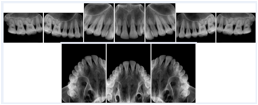

2. A patient requests cosmetic surgery to enhance their facial appearance. The case requires consultation between an orthodontist in New York and an oral surgeon in California. The cephalometric series of 2D projections constructed from a volumetric CT data set that is used for the discussion is arranged by a Structured Display for transfer between the two practitioners.

Cephalometric Series Structured Display

Figure OO-2. Cephalometric Series Structured Display